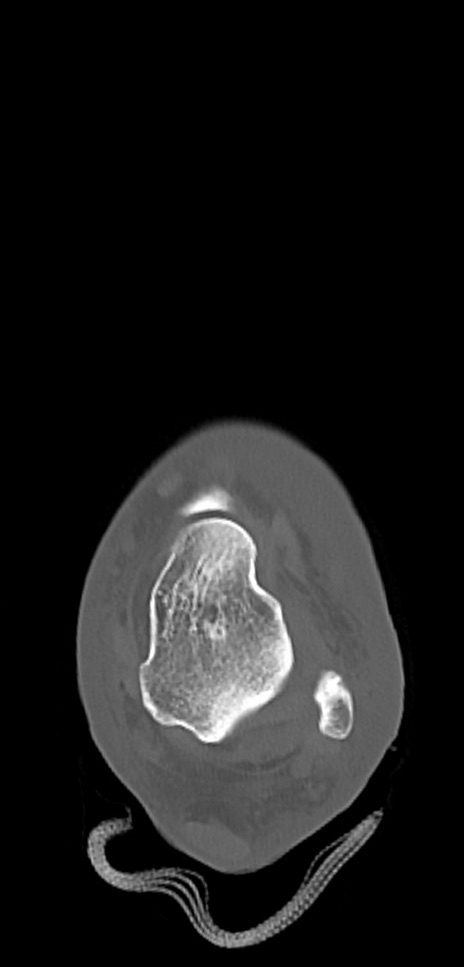

症例37 左足関節CT(横断像)

左足関節CT